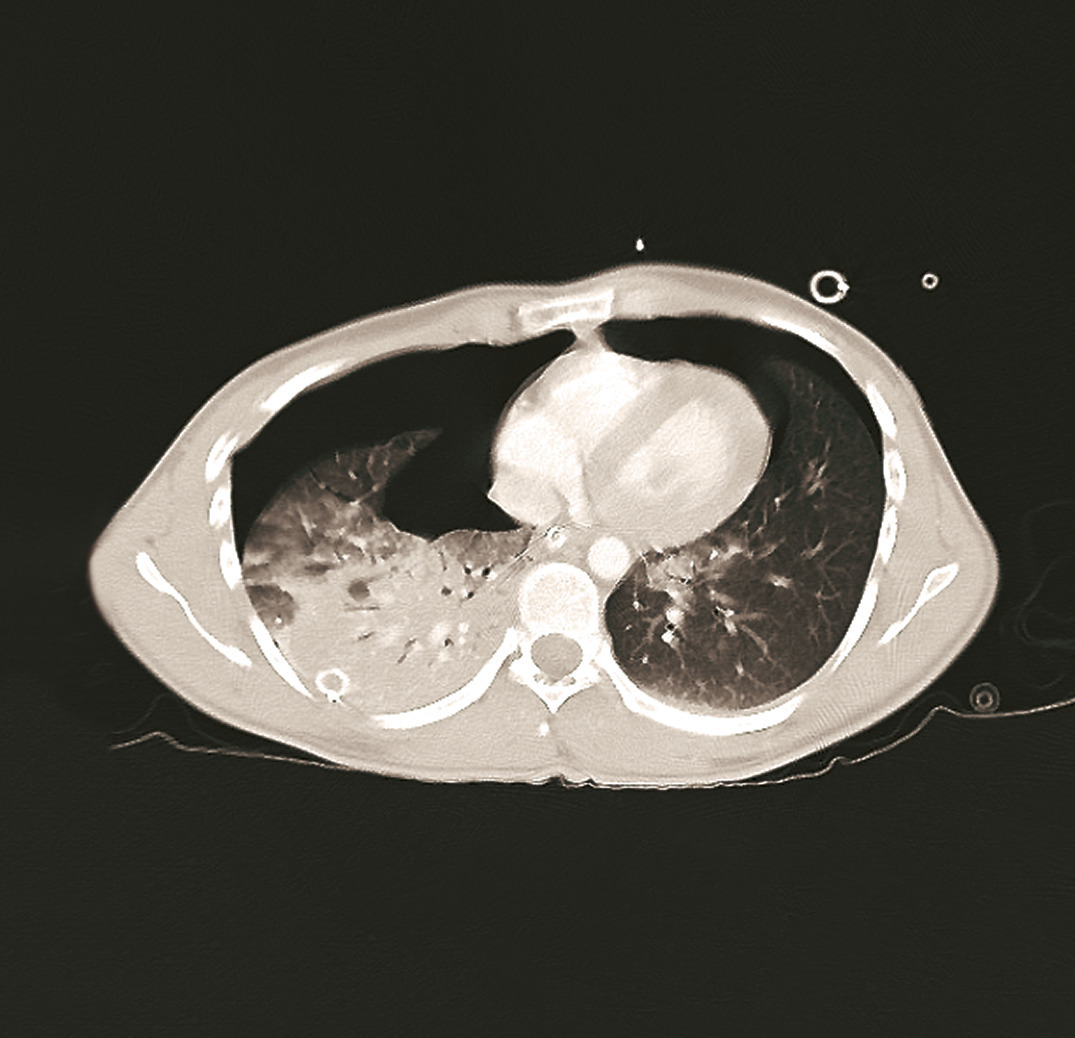

• une radiographie thoracique de face (fig. 2) pour confirmer un pneumothorax compressif ;

Pneumothorax (fig. 4)

Il est secondaire à une plaie pariétale, du parenchyme pulmonaire ou de l’arbre trachéobronchique. Il justifie un drainage s’il est complet ou mal toléré. Il peut être compressif si l’air qui entre dans la cavité pleurale y reste trappé, aboutissant à une compression des structures médiastinales et de l’hémithorax controlatéral. Il doit alors être drainé en urgence ou exsufflé par voie médio-claviculaire au 2e espace intercostal ou sur la ligne axillaire antérieure au 4e espace intercostal.